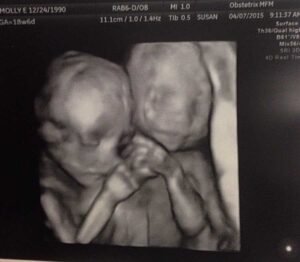

She started the ultrasound and instantly said, ‘It’s funny you should say that! It really is twins!’ She turned the screen towards me and I instantly started bawling. How in the world was I going to handle twins on top of the two babies I already have? Not only was it twins, it was identical twins. Identical? So my dream was semi right in that it was twins but because they’re identical, it can’t be one boy and one girl. My head was spinning, and I was just crying and crying. I was terrified. I felt like I was going to throw up more than I was excited.

My husband didn’t believe me over the phone. The tech had to confirm it verbally for him. This appointment I thought would take 10 minutes tops was now 45 minutes deep and throwing phrases at me like ‘maternal fetal medicine doctor’ and ‘high risk pregnancy.’ I wasn’t even the slightest bit prepared for any of it, nor did I know the absolute time commitment I would have to make in doctor offices for this pregnancy. My emotions were all over the place and so was the cereal on the floor my girls were supposed to be eating.